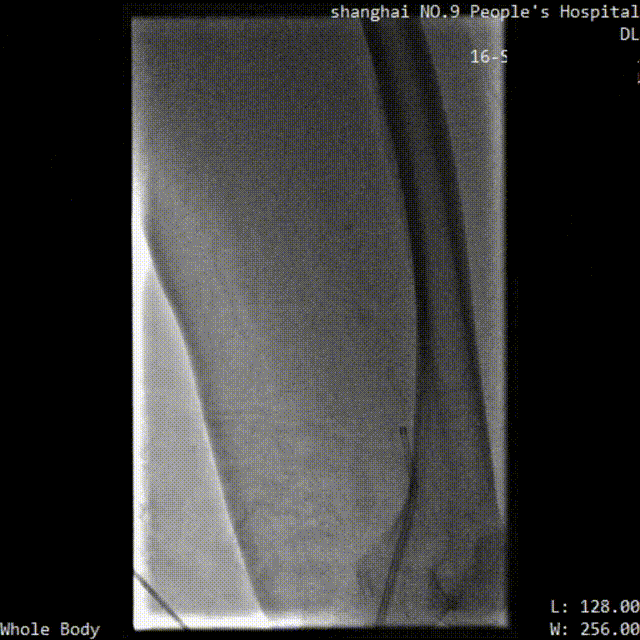

病例一

■ 基本情况:

患者,女,65岁,因“左下肢肿痛6天”入院。左下肢皮温略低,肿胀自足背至左大腿中段,呈非凹陷性水肿,Honmans征(+),左下肢深静脉血栓形成,拟行经皮机械性血栓切除术(以下简称PMT)。

■ 手术过程:

取栓术前管腔造影

术后,患者无特殊不适主诉,精神好,术肢肿胀明显消退,术肢末梢血运好,动脉搏动可扪及,双侧腓肠肌松软,双下肢感觉及运动正常。该病例随访三次,分别行超声检查及CTA检查,检查结果均良好。